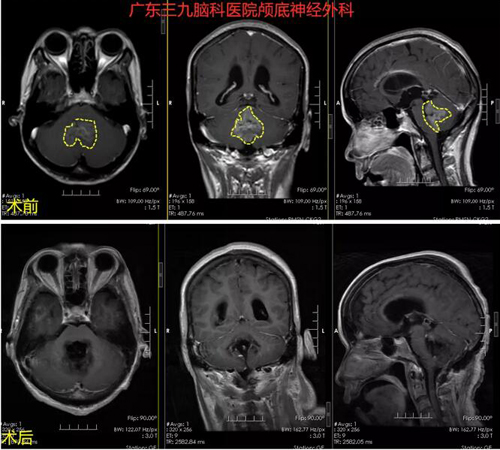

图2:术前MR示第四脑室一团占位性变病,T1W1呈低信号,T2W1呈高信号,FLAIR序列呈高信号,其内示斑片状小囊变区少许血管流空信号影,DWI序列呈不均匀高信号,ADC图呈低-稍高信号,大小约41mm*34mm*39mm。增强后病变呈不均匀轻度强化,周围小脑组织受压。脑干背侧轻度受压。双侧大脑半球皮层下白质内及双侧半卵圆中心示散在斑点状等T1长T2异常信号影,FLAIR序列呈高信号。第四脑室明显受压,幕上脑室系统明显扩张,双侧侧脑室周围示斑片状FLAIR序列高信号影。

术后MR示呈术后改变,原病变已切除。